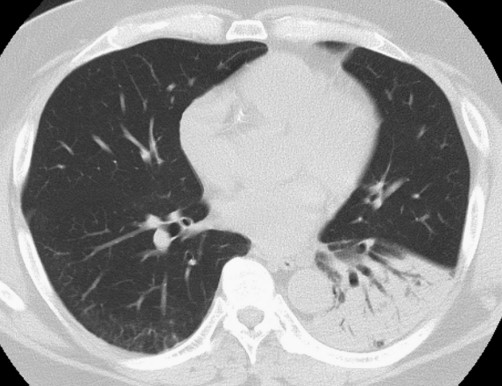

患者體格檢查無明顯異常。血液檢查顯示C反應(yīng)蛋白水平升高,1.80 mg/dL;天冬氨酸轉(zhuǎn)氨酶輕度升高,55 U/L;丙氨酸轉(zhuǎn)氨酶升高,58 U/L。其他指標(biāo)無明顯異常。血清β-D葡聚糖、人類免疫缺陷病毒(HIV)血清學(xué)和結(jié)核感染T細(xì)胞檢測(T-SPOT.TB)檢查均為陰性。高分辨率CT掃描顯示左肺下葉實變伴空氣支氣管征(圖1)

圖1 高分辨率CT掃描顯示左肺下葉實變伴空氣支氣管征